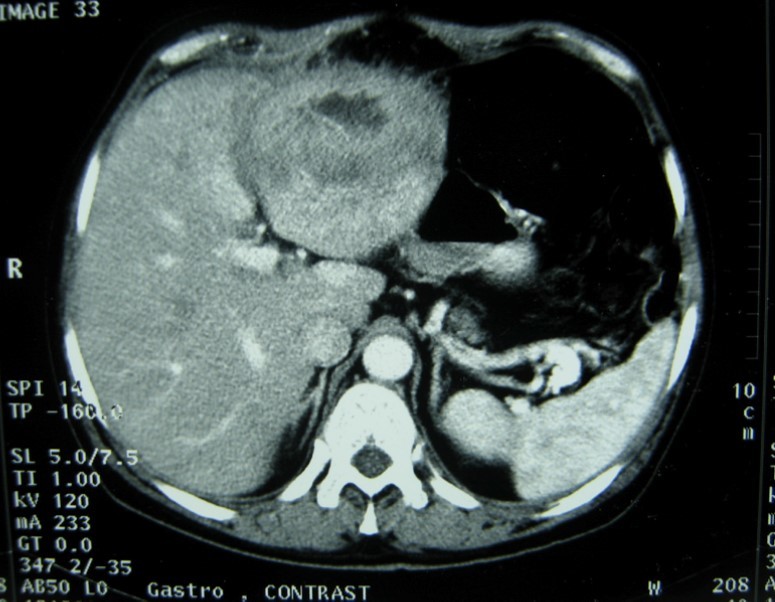

Laboratory analysis showed hemoglobin, 10.9 g/dL; white blood cell count, 9,800 cells/mm3, serum albumin, serum total bilirubin, alanine aminotransferase, aspartate aminotransferase, prothrombin time, hepatitis B surface antigen, and antibodies to hepatitis C, serum alpha-fetoprotein (AFP), carcinoembryonic antigen and carbohydrate antigen 19-9 (CA 19-9) were within normal range. Blood cultures were negative. Chest x-ray was normal. Ultrasound of abdomen showed a 10 cm hypoechogenic lesion in left liver (Figure 1). An abdominal CT showed a well-defined heterogeneous mass situated in his left hepatic lobe measuring 10 cm × 7 cm (Figure 2, Figure 3). The lesion featured central necrosis, a hyper-dense rim and a mild enrichment from the arterial phase in the CT, The diagnosis of primary hepatic tumor was suspected. An ultrasonography-guided needle biopsy of the liver was scheduled in order to rule out malignancy and to have a complete diagnosis. Cytology demonstrated a tuberculosis granuloma, acid-fast bacilli culture was positive (Figure 4). Anti-tuberculous therapy including isoniazid, rifampin, ethambutol, and pyrazinamide were prescribed. The patient completed the 6-month course of medication with success. The patient’s appetite and body weight were restored to previous levels. One year after the completion of treatment, the patient remained completely asymptomatic with disease free.

Figure 3.Abdominal computed tomography with intravenous contrast showing the lesion with ring enhancement.

Computed tomography (CT) and magnetic resonance imaging (MRI) are helpful in diagnosis.

CT findings of tuberculosis abscesses can show low-density focal lesions with or without ring enhancement on contrast administration. These have also been seen in necrotic tumor such as hepatocellular, inflammatory disease and metastatic carcinoma 12.